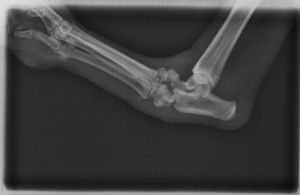

Artrodesis

Es una cirugía que consiste en fusionar articulaciones que tienen problemas de inestabilidad, dolor o artrosis, para eliminar el dolor y tener una buena funcionalidad y calidad de vida.

Se colocan placas especiales con tornillos, que adaptados a la forma que queremos que la articulación adopte una vez fusionada.